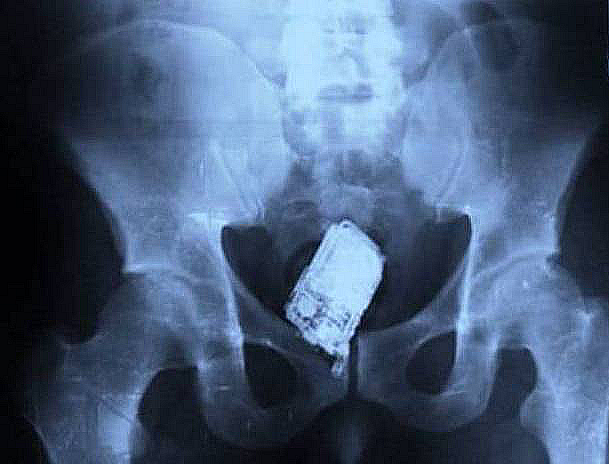

A cellphone

viralscape.com

Image Source: viralscape.com

A prisoner in Salvador tried to smuggle a cellphone in his you-know-what. Nedless to say, he was caught in a rather uncomfortable position.